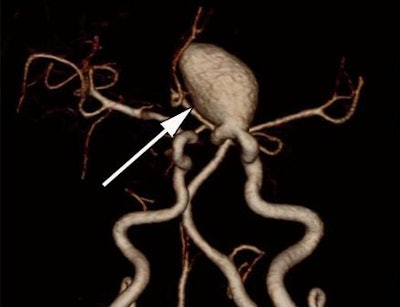

Volume-rendered image (above) and maximum-intensity-projection image (below) from a 47-year-old woman with a left internal carotid aneurysm (arrows). Images courtesy of Radiology.

Nonsubtracted volumetric CTA had a comparable diagnostic ability to subtracted volumetric CTA and 3D DSA for detecting aneurysms of the anterior communicating artery, the posterior communicating artery, the anterior cerebral artery, and the middle cerebral artery, the researchers found.

"The aneurysms missed at nonsubtracted volumetric CT angiography were generally located in the internal carotid artery," they wrote. "Detection of cerebral aneurysms adjacent to bone tissue was still challenging at nonsubtracted volumetric CT angiography because of the presence of overlying bone structures."